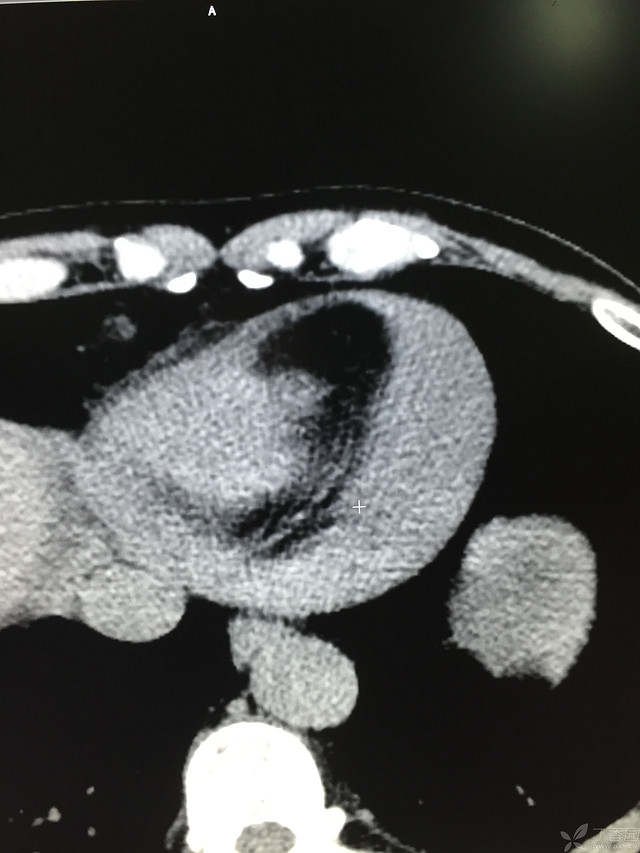

胸痛三天,加重三小时(CT是心包高密度影是什么)

患者性别:男

患者年龄:64岁

简要病史:三天前休息时突发胸前区疼痛伴大汗,到当地医院输液治疗后缓解,3小时前情绪激动后再次出现胸痛伴大汗,胸部压迫感,持续不缓解入院,到当地医院测血压180/?mmHg泵入硝酸甘油转入我院。

体格检查:血压94/72mmHg(右侧)96/74mmHg(左侧),心率78此/分,其他未见阳性体征